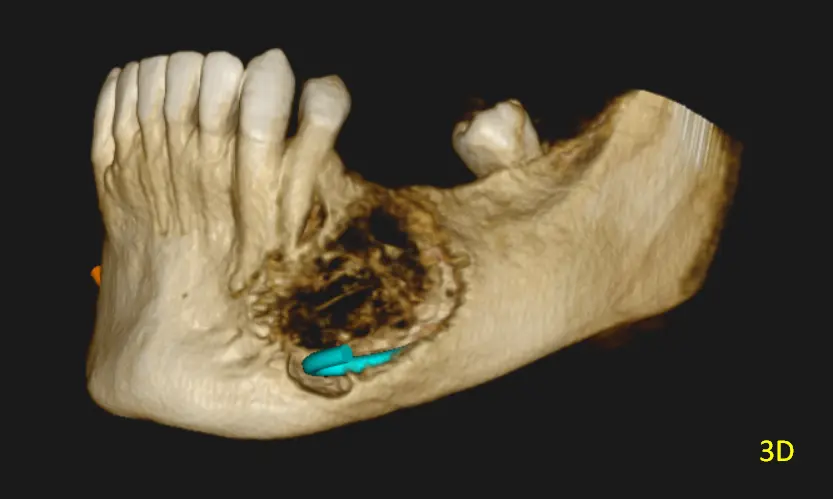

En las reconstrucciones 3D y cortes multiplanares (ver Fig 1, 2 y 3) se observa lesión oseteolítica extensa con ausencia de una capsula definida, ubicada en el cuerpo mandibular, lado izquierdo, zona de premolares.

Presenta tabiques óseos finos que delimitan compartimentos irregulares con expansión y adelgazamiento de las corticales óseas, con áreas de compromiso cortical. La relación cercana con el conducto dentario inferior, sin evidencia clara de invasión, pero con desplazamiento y borramiento en sectores de dicha pared del conducto.